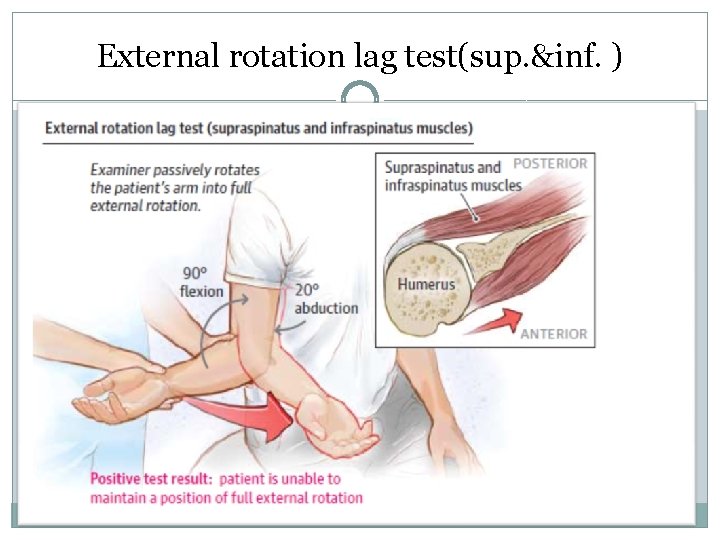

External rotation lag test(sup. &inf. )